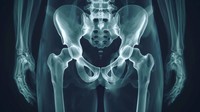

La symphyse pubienne est une articulation cartilagineuse située à l'avant du bassin, reliant les deux os pubiens. Elle joue un rôle clé dans la stabilité du bassin, en permettant une légère mobilité pour absorber les chocs et faciliter des mouvements tels que la marche.